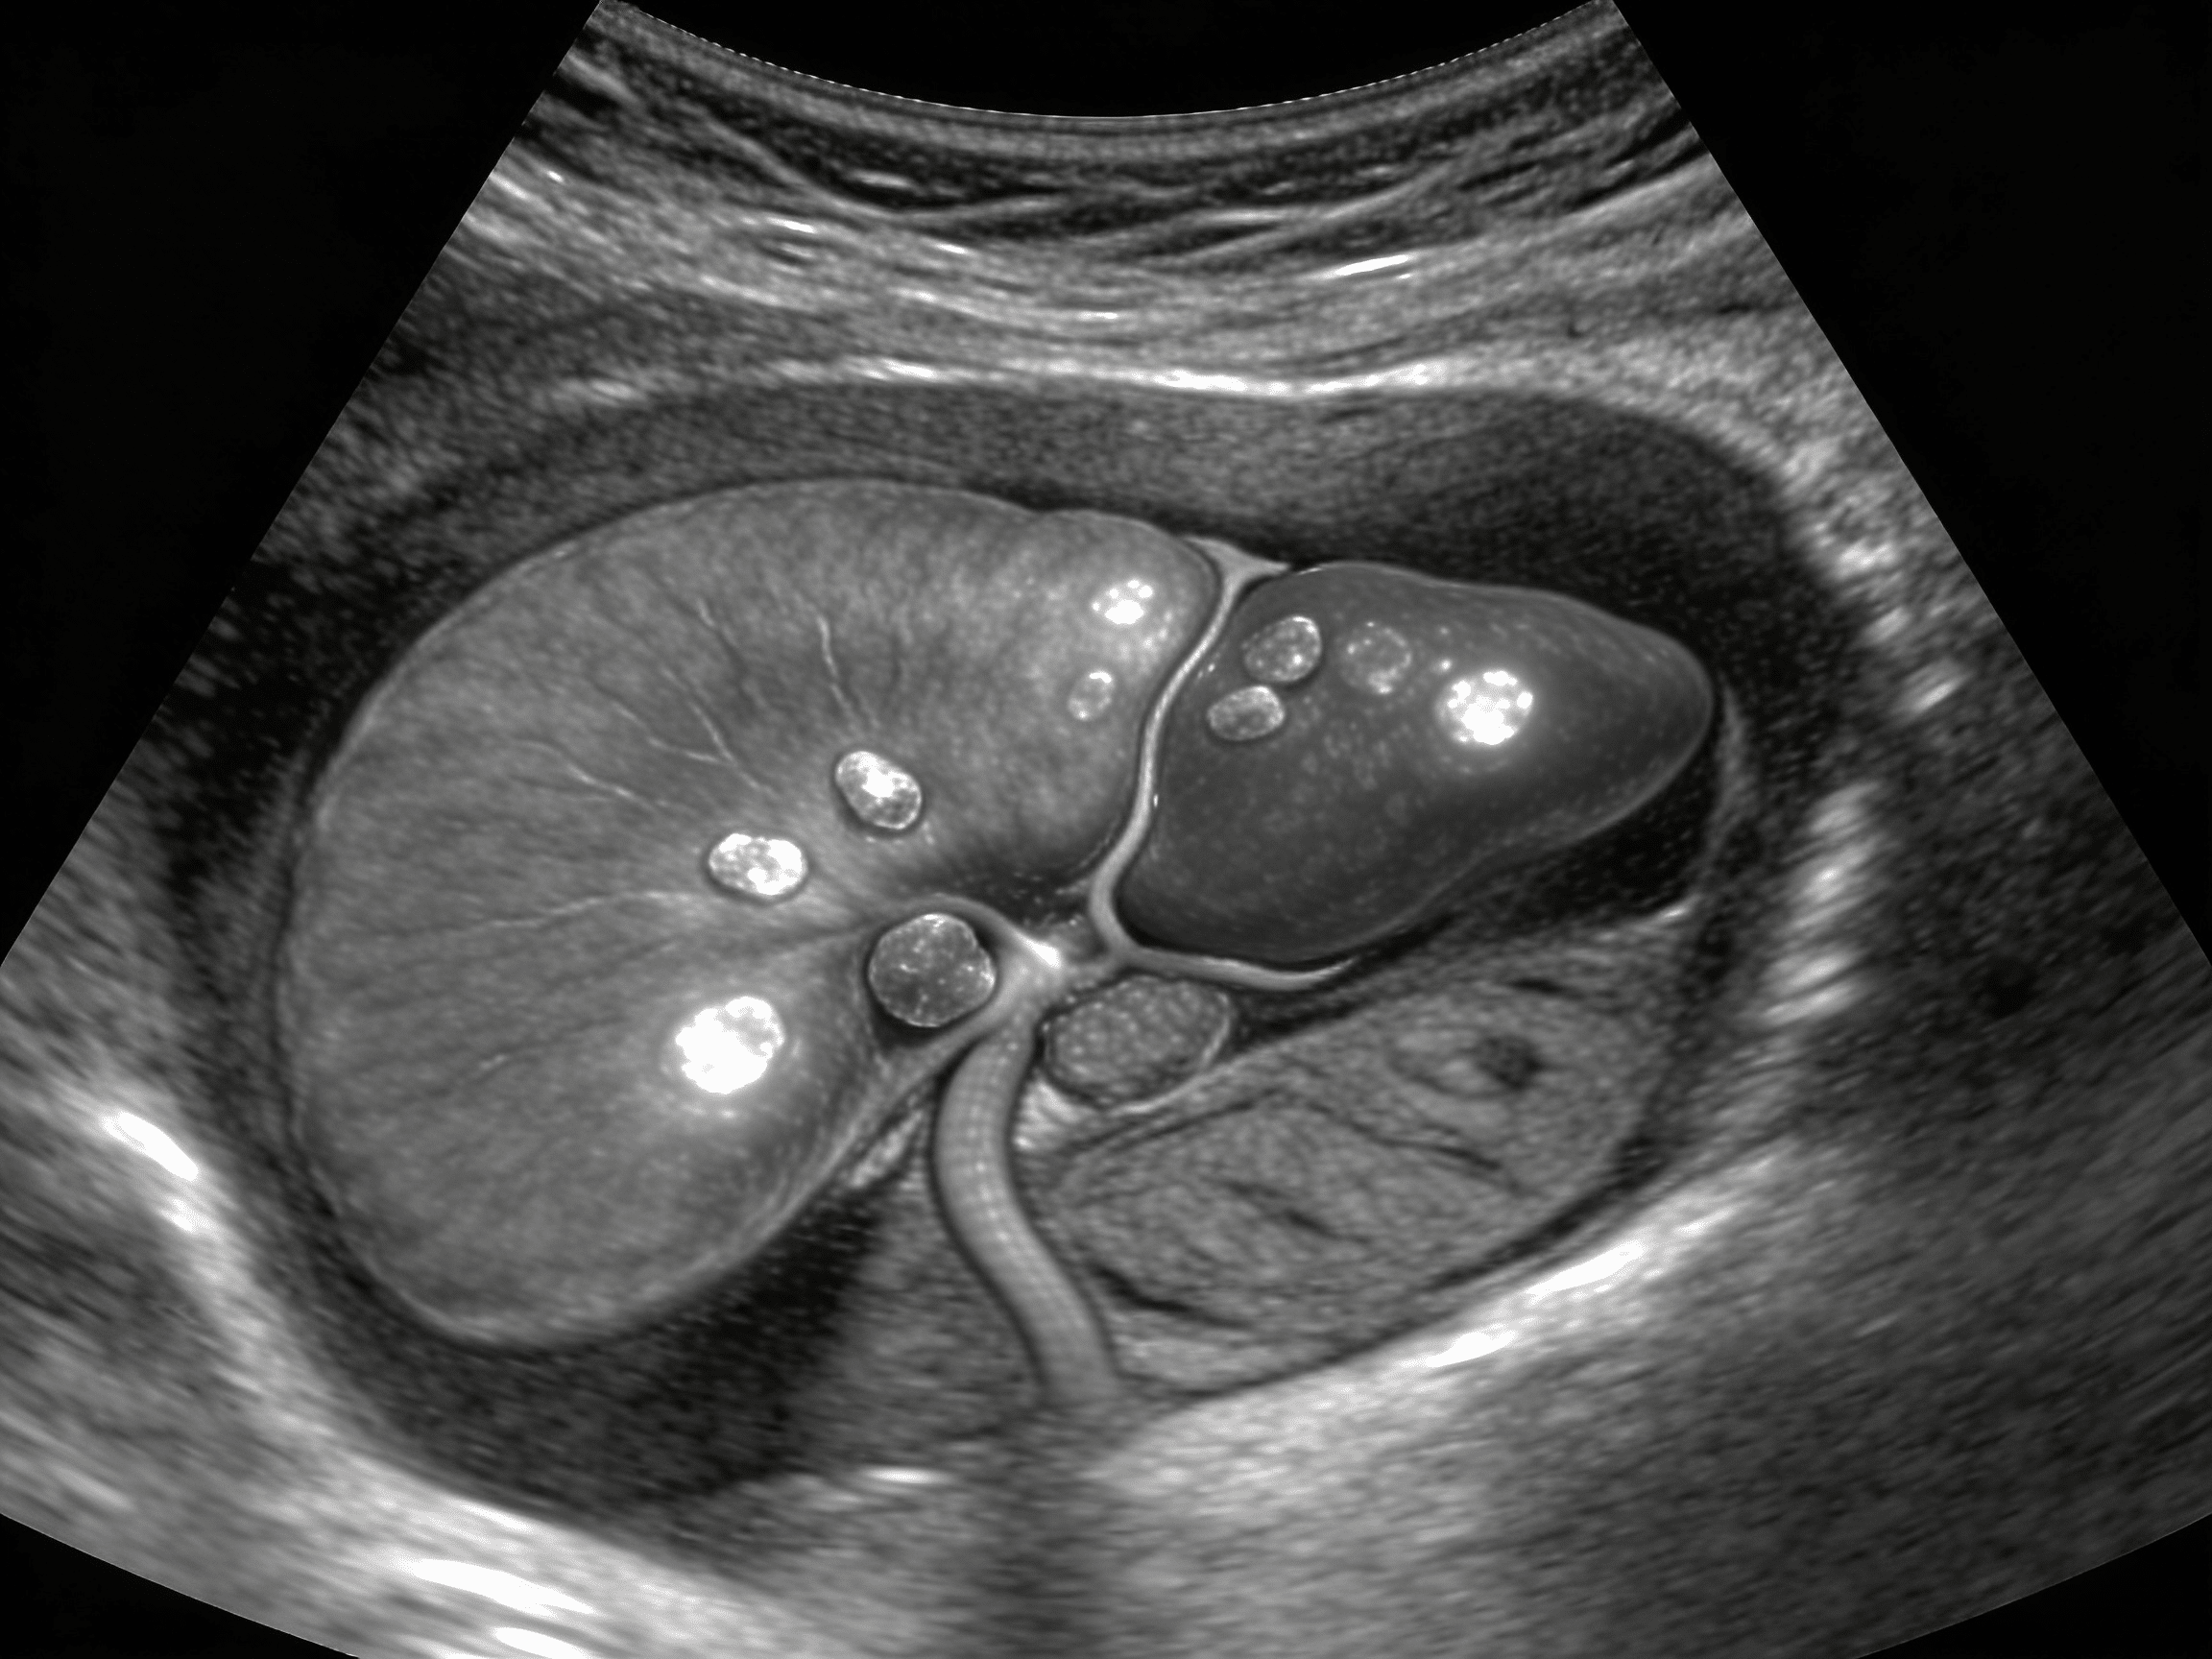

What does acute cholecystitis look like on ultrasound?

Acute cholecystitis on ultrasound shows gallbladder wall thickening >4mm, pericholecystic fluid, gallbladder distention, gallstones (95% of cases), and positive sonographic Murphy's sign (maximal tenderness when ultrasound probe pressed over gallbladder). Priority ER emergency physicians identify these findings with 88% sensitivity, immediately differentiating acute cholecystitis requiring surgery from biliary colic (gallstones without inflammation) requiring pain management and elective cholecystectomy. Emphysematous cholecystitis shows gas in gallbladder wall indicating life-threatening infection requiring emergency surgery, while acalculous cholecystitis (no stones) occurs in critically ill patients requiring different management approach.

The Permian Basin's occupational hazards and motor vehicle accidents increase trauma rates requiring immediate FAST examination, while prolonged sitting in vehicles for oil field workers elevates DVT risk by 52% compared to general population[13]. Our surgical emergency capabilities include immediate general surgery consultation when ultrasound identifies acute cholecystitis with thickened gallbladder wall >4mm, pericholecystic fluid, sonographic Murphy's sign, or gallbladder distention indicating surgical emergency requiring laparoscopic cholecystectomy within 24-48 hours preventing perforation and peritonitis. Additionally, the region's aging population faces increasing risks of provoked DVT from cancer-associated thrombosis, with occult malignancies presenting initially as DVT requiring thorough evaluation when Wells criteria suggest unprovoked thrombosis in patients without obvious risk factors.